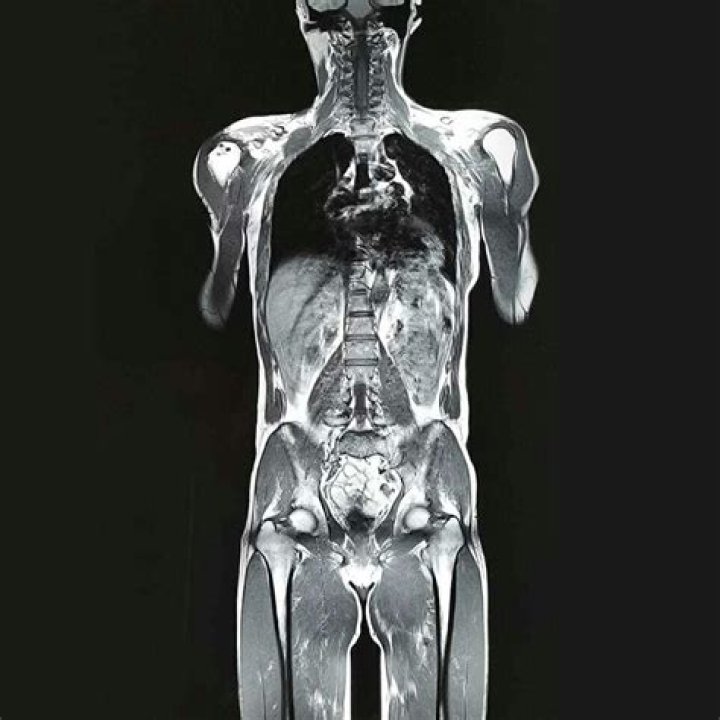

Are full body MRI scans worth it?

A whole body MRI screening can help detect possible cancer lesions, aneurysms (blood vessel blockages), bone and joint issues, and spine problems inside your body. An MRI scan of the head and spinal cord may help detect: Brain injuries. Blood vessel damage.

What will a full body MRI show?

A whole-body MRI scan looks at the body from head to toe in order to find cancers, inflammation or obstructive processes in the body. In the head, the exam can show brain masses, shrinkage, old strokes, the sinuses and nasal cavities.